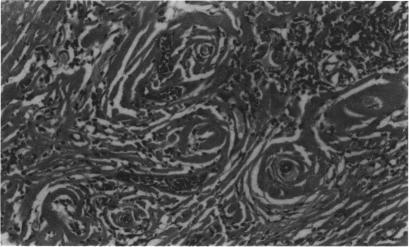

Multifocal fibrosclerosis is a condition of unknown aetiology, characterised by fibrous lesions occurring at a variety of sites. Clinical variants include retroperitoneal fibrosis, Riedel's thyroiditis, sclerosing cholangitis, and mediastinal fibrosis. Orbital pseudotumour has been reported as a manifestation of this condition. Three patients with multifocal fibrosclerosis in whom orbital involvement was the dominant feature are described.

多灶性纤维硬化是一种病因不明的病症,其特征是在多个部位出现纤维性病变。临床变体包括腹膜后纤维化、Riedel甲状腺炎、硬化性胆管炎和纵隔纤维化。眼眶假瘤已被报道为这种病症的一种表现形式。本文描述了3例以眼眶受累为主要特征的多灶性纤维硬化患者。